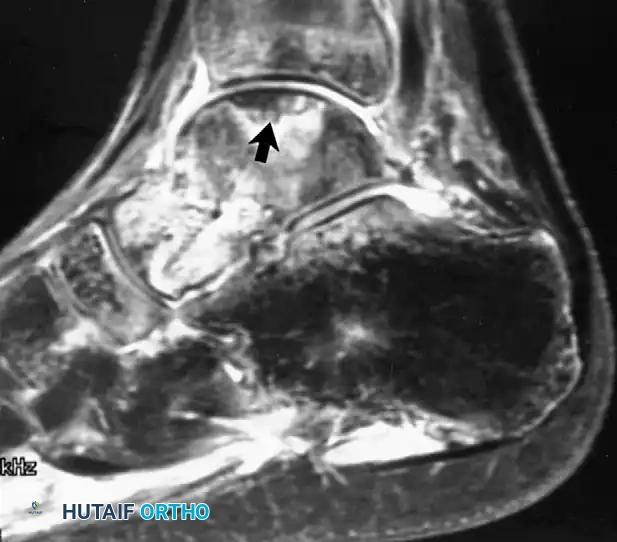

Fig. 2-5 Osteonecrosis of talus. Fat-suppressed proton density–weighted image reveals focus of abnormal signal in talar dome after fracture of talar neck.